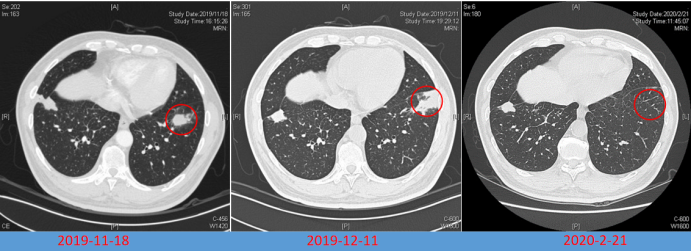

病例5:男性,64岁,主因“咳嗽、咳痰伴双肺多发阴影3个月,咯血1天”于2019年11月14日入院。7月23日因多发肺部结节影,诊断肺结核,予四联抗结核治疗。10月29日因糖尿病酮症酸中毒于我院普内科住院,期间查胸部CT提示双侧胸腔积液,心影增大,考虑合并心功能不全,对症治疗后好转出院。11月13日患者突发咯血,20~30口,鲜血,收入呼吸内科病房。借助导航支气管镜获取组织标本,经冷冻肺活检发现组织内有大量菌丝,同时送检的mNGS检测到毛霉序列,通过组织病理联合组织mNGS,真正意义上实现了毛霉病的确诊。因患者拒绝全身用药,遂实施局部用药方案。在导航支气管镜与超声技术的辅助下精准定位病灶后,对其进行两性霉素B的精准局部灌注治疗。经过两次该治疗,病灶成功消失(图5)

图片

5  病例5治疗前后胸部CT比较